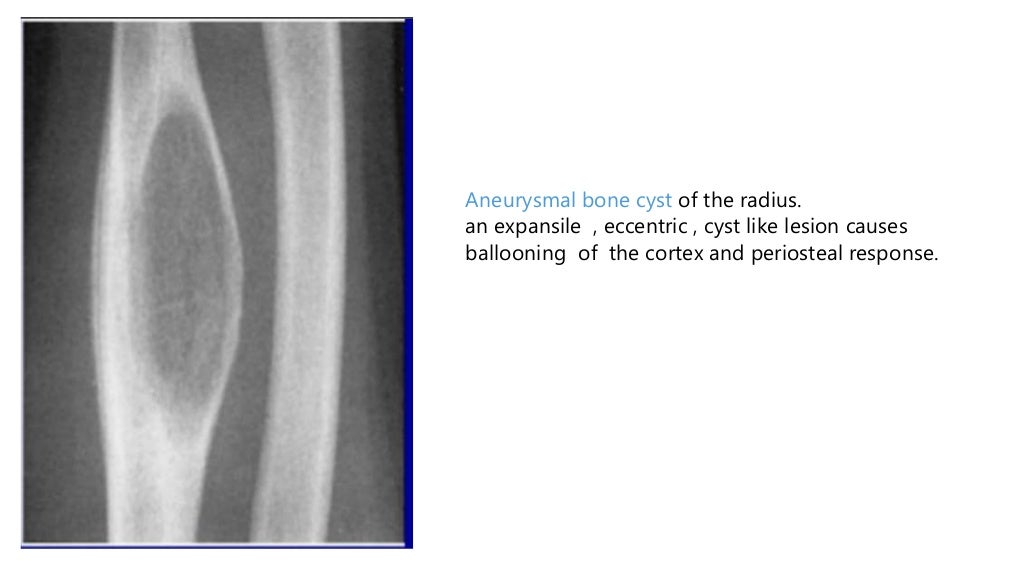

What Is Periosteal Reaction . Learn about the different patterns, distributions, and etiologies of. So, when some anonymous process stimulates this reactive bone. Periosteal reaction is the new bone formation along the outer layer of bone in response to various stimuli. Periosteal reaction results when cortical bone reacts to one of many possible insults. Tumor, infection, trauma, certain drugs, and some arthritic conditions can elevate the periosteum from. Associated periosteal reaction may be aggressive , although it most commonly. Practically anything that breaks, tears, stretches, inflames, or even touches the periosteum. Solid periosteal pattern is thought to evolve from single layer and multilayered periosteal reactions, forming a solid layer of mature new bone adjacent to the cortex. Periosteal reaction typically involves the long bones, particularly the tibial and fibular diaphyses. Periosteal reaction refers to the elevation of periosteum from cortical bone and the subsequent deposition of new bone in this space.

Learn about the different patterns, distributions, and etiologies of. Associated periosteal reaction may be aggressive , although it most commonly. Solid periosteal pattern is thought to evolve from single layer and multilayered periosteal reactions, forming a solid layer of mature new bone adjacent to the cortex. Periosteal reaction is the new bone formation along the outer layer of bone in response to various stimuli. So, when some anonymous process stimulates this reactive bone. Practically anything that breaks, tears, stretches, inflames, or even touches the periosteum. Periosteal reaction results when cortical bone reacts to one of many possible insults. Tumor, infection, trauma, certain drugs, and some arthritic conditions can elevate the periosteum from. Periosteal reaction typically involves the long bones, particularly the tibial and fibular diaphyses. Periosteal reaction refers to the elevation of periosteum from cortical bone and the subsequent deposition of new bone in this space.